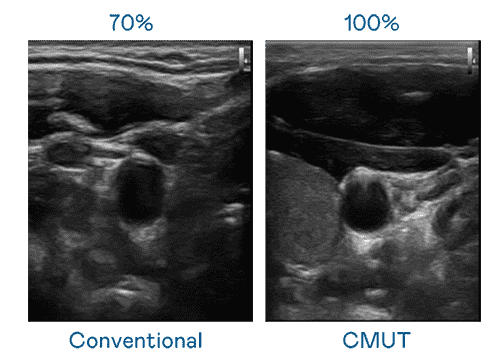

CMUT 技术是一种用电容式微机电元件来产生超音波讯号的技术。。。与传统 PZT 压电式技术相比,,,CMUT 频宽增加 30%,,,,更宽频的超音波讯号让影像解析度大幅提升,,,,是实现高影像品质医疗超音波扫描、、促进精准医疗发展的关键技术。。。

大频宽带来超清晰影像

超音波影像的解析度高低,,首先取决于探头能发出的讯号频宽。。EBpay CMUT 可提供高清晰的超音波讯号,,提供高频宽、、、高灵敏度、、、、影像纹理细节更高的超音波影像,,,协助医护人员缩短影像判读时间及利用精准的医疗影像进行诊断。。。